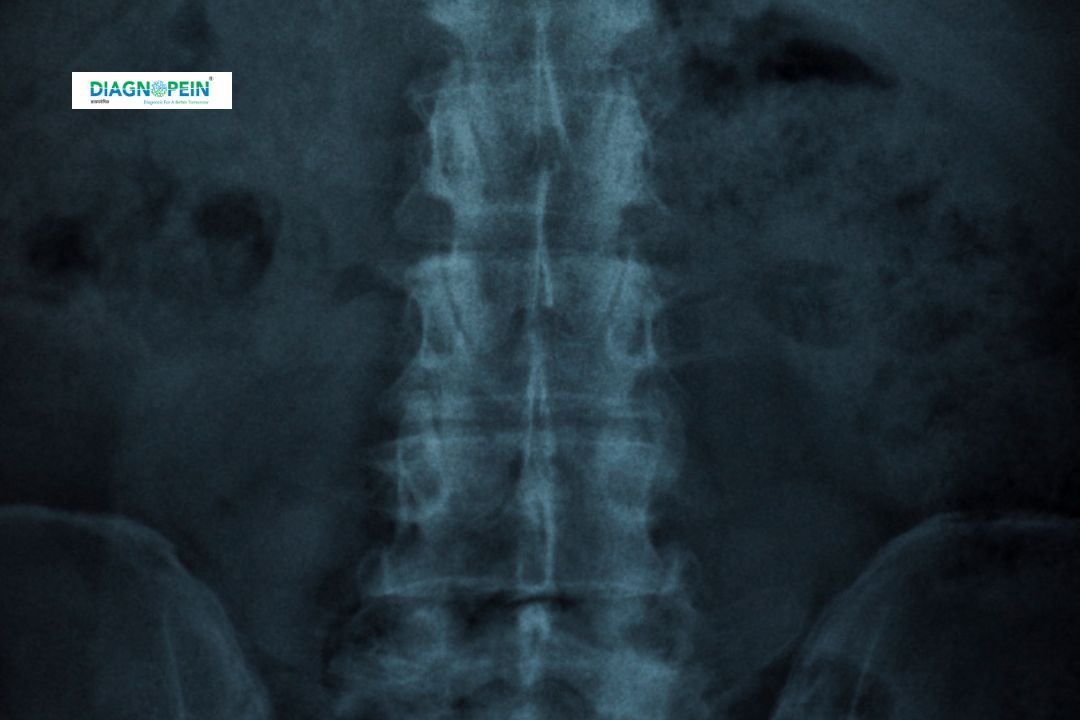

The PNS (Plain) Test, also called the Paranasal Sinus X-Ray, is a simple and effective diagnostic imaging process that helps visualize the air-filled spaces around the nose and eyes. This procedure is crucial for identifying sinus infections, inflammations, structural deformities, or any blockages that may cause discomfort.

PNS (Plain) X-Ray is often recommended by ENT specialists to diagnose chronic sinusitis, nasal obstruction, allergies, and structural abnormalities like a deviated septum. It is valuable because it is fast, affordable, and delivers immediate results.